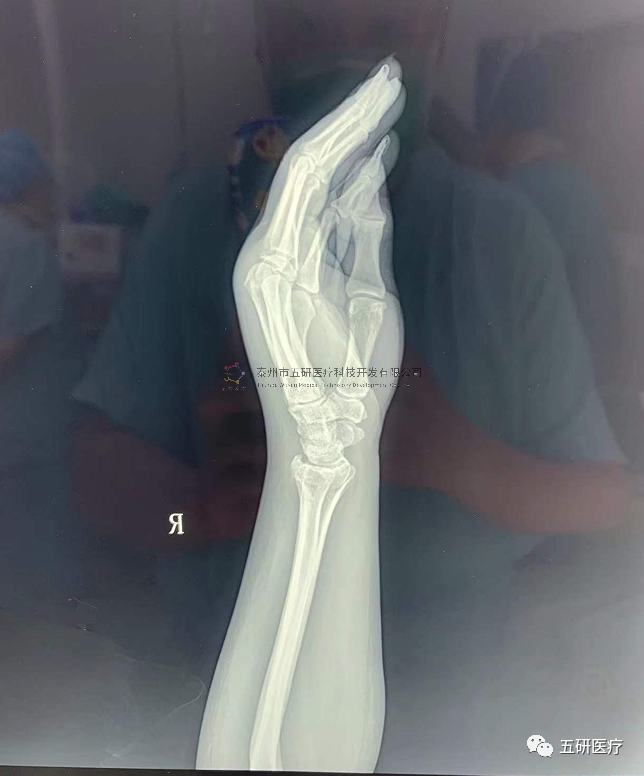

// 腕架

本病例由中國中醫(yī)科學(xué)院望京醫(yī)院骨綜科提供(術(shù)者:支架醫(yī)生常醫(yī)師)

【基本資料】患者,女,61歲

本病例腕架骨折。術(shù)前正側(cè)位片:右橈骨遠端骨折。

采用常規(guī)方法固定,自掌骨尺側(cè),約基底稍偏遠處穿入螺紋針。

外架馬蹄環(huán)穿過骨針,更方便調(diào)整固定角度。